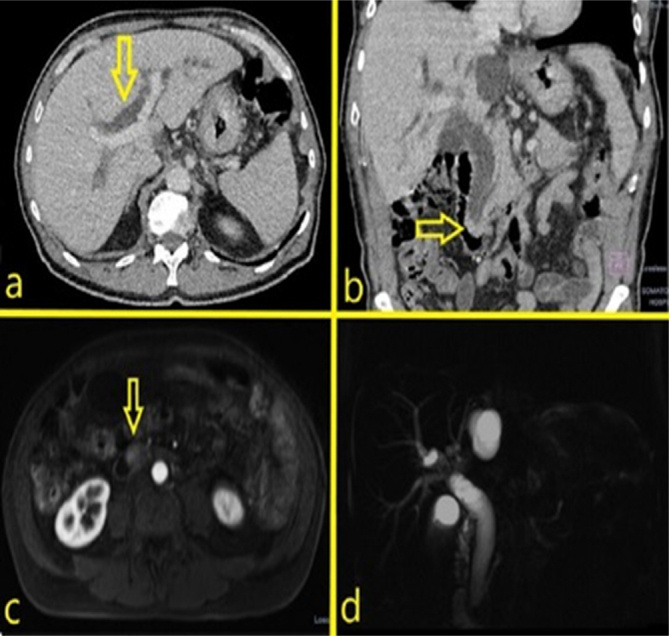

Mixed neuroendocrine-non-neuroendocrine tumors (MiNEN) are a rare type of tumor formed by two components, a non-neuroendocrine component that is most often an adenocarcinoma and a neuroendocrine tumor, and each of these components must represent at least 30% of the tumor. The origin of this tumor on the ampulla of Vater or periampullary region is more infrequent. Usually, the lesions are highly aggressive and quickly metastasizing, and their biological behavior is dictated by the high grade of the neuroendocrine component. This is the first report of a patient with ampullary MiNEN treated employing a robotic pancreaticoduodenectomy. Although being submitted to aggressive treatment with complete surgical resection followed by systemic therapy, the patient developed early recurrence with hepatic metastatic disease, demonstrating the hostile nature of these tumors.